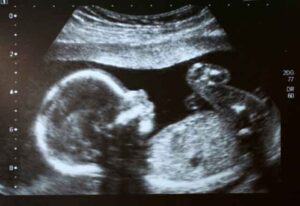

Si chiama FUS (Focused Ultrasound Surger), Chirurgia a Ultrasuoni Focalizzati, ed è un'attrezzatura del valore di 1.250.000 euro che da...